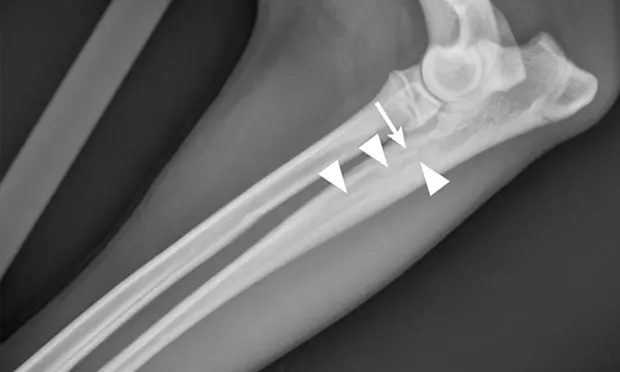

Radiographic signs of panosteitis frequently lag days to weeks behind clinical signs.1,3 The earliest radiographic sign of panosteitis is a decrease in opacity around the nutrient foramen. Later signs include an increase in mineral opacity within the medullary canal of long bones and loss of the normal trabecular bone pattern (Figure 1). Smooth periosteal and endosteal new bone may also be seen in more severe cases (Figure 2). Radiographs of the affected limb may be compared with those of the contralateral limb to assist in diagnosis. Nuclear scintigraphy may assist in diagnosis in cases in which radiographic changes have not yet developed.4

Lateral radiographic projections of the femur (A) and ulna (B, next slide) in dogs with early signs of panosteitis. Note the radiolucency around the nutrient foramen (arrows) and increased opacity within the medullary canal (arrowheads) in both cases.